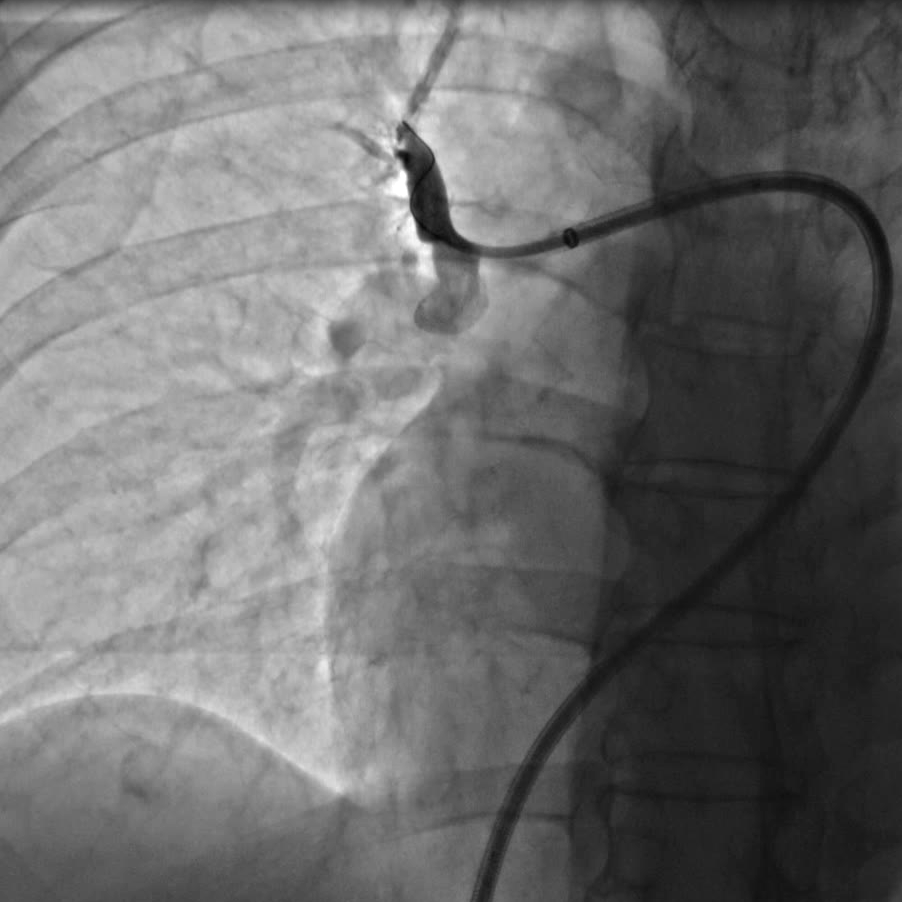

指引导管右肺A1段造影提示A1段近段次全闭塞

手术由心脏中心主任马翔、副主任医师吕文魁及戴远辉完成,团队分别依次对患者右肺动脉A10段、A5段、A1段行球囊扩张,先用2.0mm的球囊以6—12atm扩张,再使用3.0mm的球囊逐级扩张,球囊扩张后患者胸闷症状即刻好转,术后8小时已下地行走,目前各方面生理指标达到预期,即将出院。